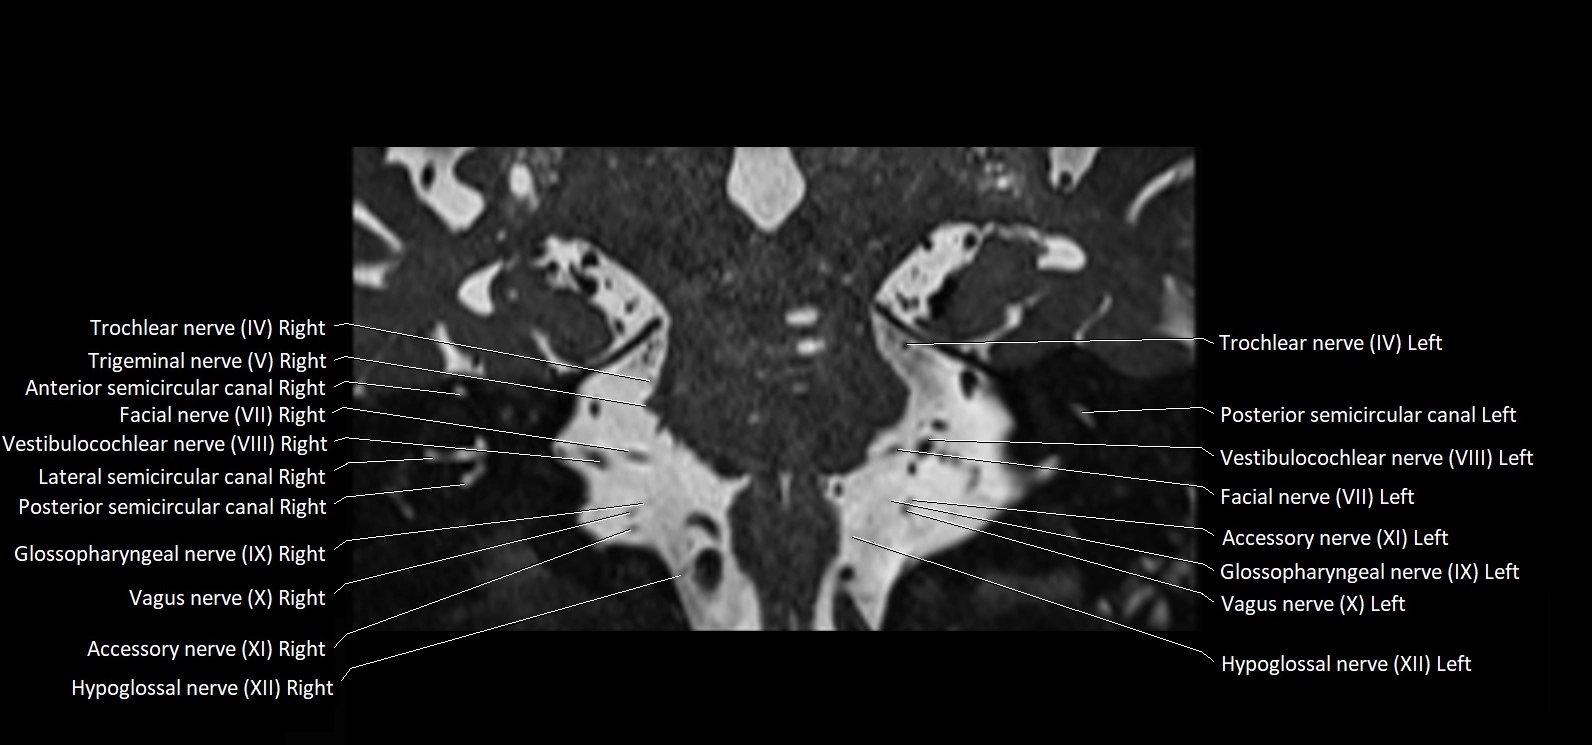

MRI images

image